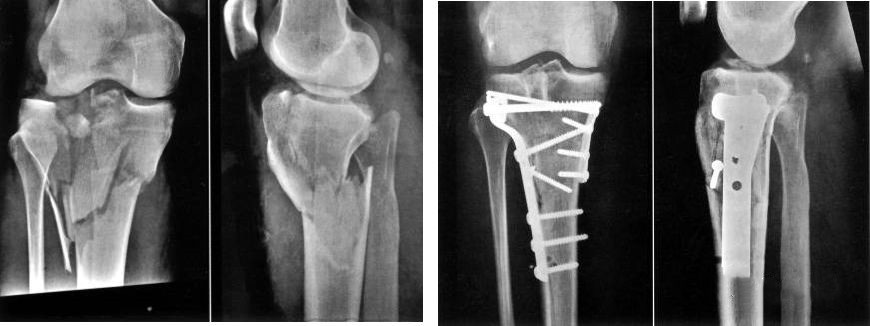

Определить характер травмы насилием

Высокоэнергетическая травма часто сопровождается тяжелым повреждением мягких тканей.Он характеризуется отеком конечностей, образованием волдырей, ссадин и разрывов кожи.Операцию следует отложить на это время.При этом необходимо исключить синдром фасциального пространства и повреждения сосудов и нервов.

Особенность анатомии – важность покрытия мягкими тканями.

Ранняя стадия: в течение 8 часов

Внешний фиксатор считается первым выбором для раннего лечения.

Гипсовая опора

Вытяжение пяточной кости

Фаза II: около 2 недель.

Явной системной инфекции и острой травмы не было.

Отечности и экссудации раны нет.

Волдырь подсох, опухоль спадает, костные маркеры можно трогать.

Морщинистая кожа, появляются морщины.

Результат лечения перелома пилона зависит от качества реконструкции сустава и состояния мягких тканей.